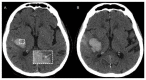

Intracerebral hemorrhage (ICH) accounts for 10% to 20% of all strokes worldwide and is associated with high morbidity and mortality. Neuroimaging is clinically important for the rapid diagnosis of ICH and underlying etiologies, but also for identification of ICH expansion, often as-sociated with an increased risk for poor outcome. In this context, rapid assessment of early hema-toma expansion risk is both an opportunity for therapeutic intervention and a potential hazard for hematoma evacuation surgery. In this review, we provide an overview of the current literature surrounding the use of multimodal neuroimaging of ICH for etiological diagnosis, prediction of early hematoma expansion, and prognostication of neurological outcome. Specifically, we discuss standard imaging using computed tomography, the value of different vascular imaging modalities to identify underlying causes and present recent advances in magnetic resonance imaging and computed tomography perfusion.